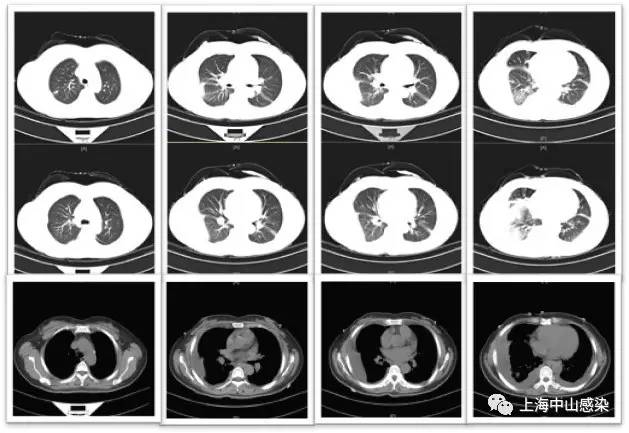

6月14日复查胸部CT2:肺炎稍吸收,但双侧胸腔积液更加明显

肺吸虫血清抗体阳性,诊为肺吸虫病,吡 喹酮1g(200mg*5片),tid,3天,8.29 CT3复查病灶明显吸收。